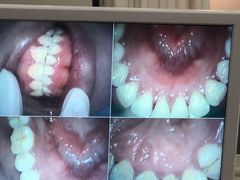

• 牙博士口腔品牌连锁(杨浦店)

• -牙博士口腔品牌连锁(杨浦店)

聂艳艳_6386 | 22-06-30

阿妮达 | 22-06-30